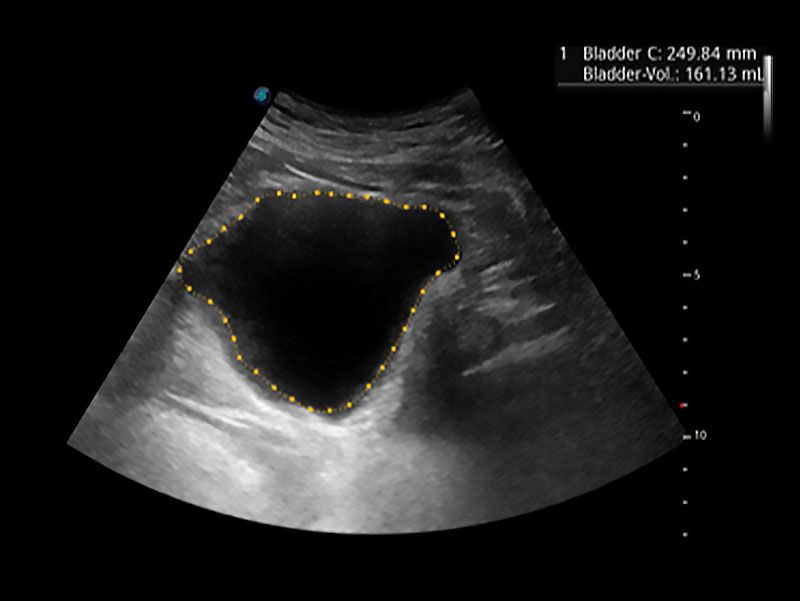

一键自动识别膀胱壁及自动测量膀胱容积,不受膀胱形状和大小的限制,帮助医生快速精准获得测量的数据。